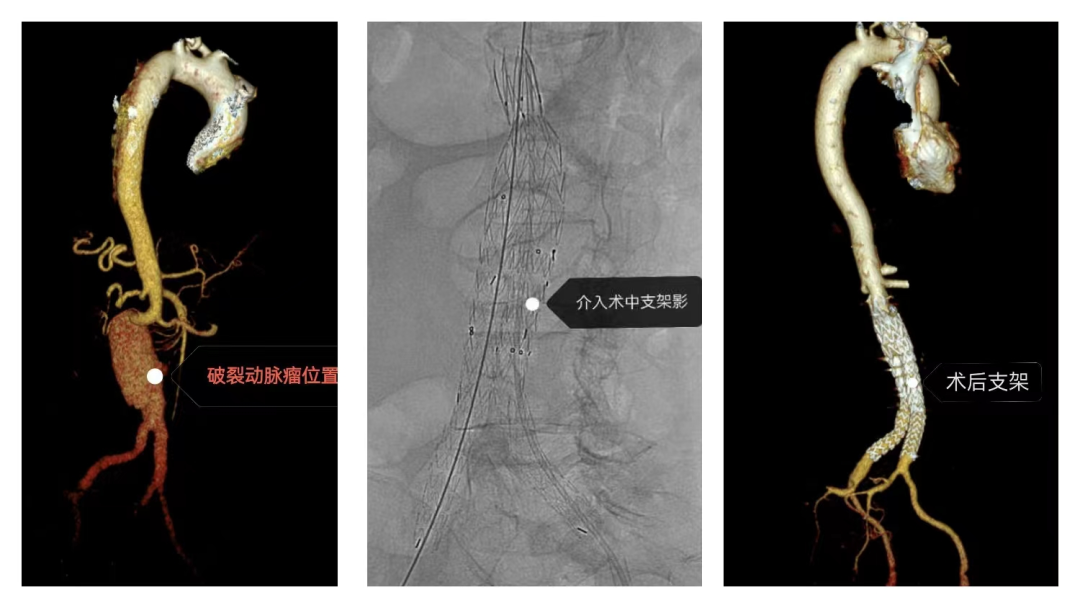

人民医院急诊科接到了转送来的患者黄女士,患者因下腹部撕裂样疼痛入院,接诊医生认真询问病史及查体,警觉发现病情复杂,在行全主动脉CTA检查时,迅速联系医务科启动“绿色通道”,请心胸外科、重症医学科、麻醉科急会诊。CTA图像显示,患者腹主动脉瘤已经出现破裂,腹腔大量积血,血管条件极差,生命危在旦夕。心胸外科曾伟生教授和闫玉生教授在查看报告后,考虑病情紧急,必须立即手术,与患者及家属充分沟通后,决定立即行腹主动脉瘤覆膜支架腔内隔绝术封堵破口。 手术难度大、风险高,闫玉生教授率领心胸外科团队,联合重症医学科、急诊科、放射科、介入室、麻醉科等多个学科,研究讨论手术方案、准备手术,经过紧张周密的术前准备工作,在当天下午就为患者开展手术。在麻醉科行气管插管全麻后行腹主动脉瘤覆膜支架隔绝术+双侧髂总动脉腔内隔绝术,手术中,黄女士因破裂口位于主干道上,出血量大,一度出现血压及心率持续下降的危情,闫玉生教授及其团队有条不紊,想尽办法维持患者血压心率稳定,并精准地释放支架阻断了破口,争分夺秒与“死神”赛跑,在心胸团队和多学科的通力合作下,经过6个多小时手术,患者成功脱离生命危险。 经过半个月的悉心治疗,黄女士在7月10日顺利出院。“术后的康复很关键,出院后至少三个月到半年不能剧烈运动,注意休息,保持良好生活习惯,记得按时随访复查……“”闫教授对黄女士及家属仔细叮嘱注意事项。 据介绍,腹主动脉瘤破裂(rAAA)是一种致死率相当高的疾病,死亡率高达85%,约2/3的患者在到达医院前死亡,对于存活下来接受手术的患者,围手术期死亡率仍高达41%~48%,被医学界称为藏在人体腹腔的“定时炸弹”。闫教授提醒,大多数腹主动脉瘤患者在血管破裂之前几乎没有症状,或者轻微腹痛不适,很容易被忽视,预防腹主动脉瘤要养成良好的生活习惯,积极控制高血压、高血脂、动脉硬化等危险因素,戒烟等。一旦发现腹主动脉瘤,应积极控制血压,稳定情绪,避免用力咳嗽、血压波动等,以最大限度降低动脉瘤的破裂风险,同时应就近及时就医。 “这次成功的转诊救治案例,展现了我市医共体的高效协同救治能力,也凸显了医共体总院特聘专家教授团队人才资源和技术优势,在这种机制联动配合下,医疗服务跑出了“加速度”,患者在家门口就能得到更及时更精准的救治。”市人民医院名誉院长、特聘教授曾伟生说。 实施此类比肩省级大型医院技术的高难度手术,在时光直播